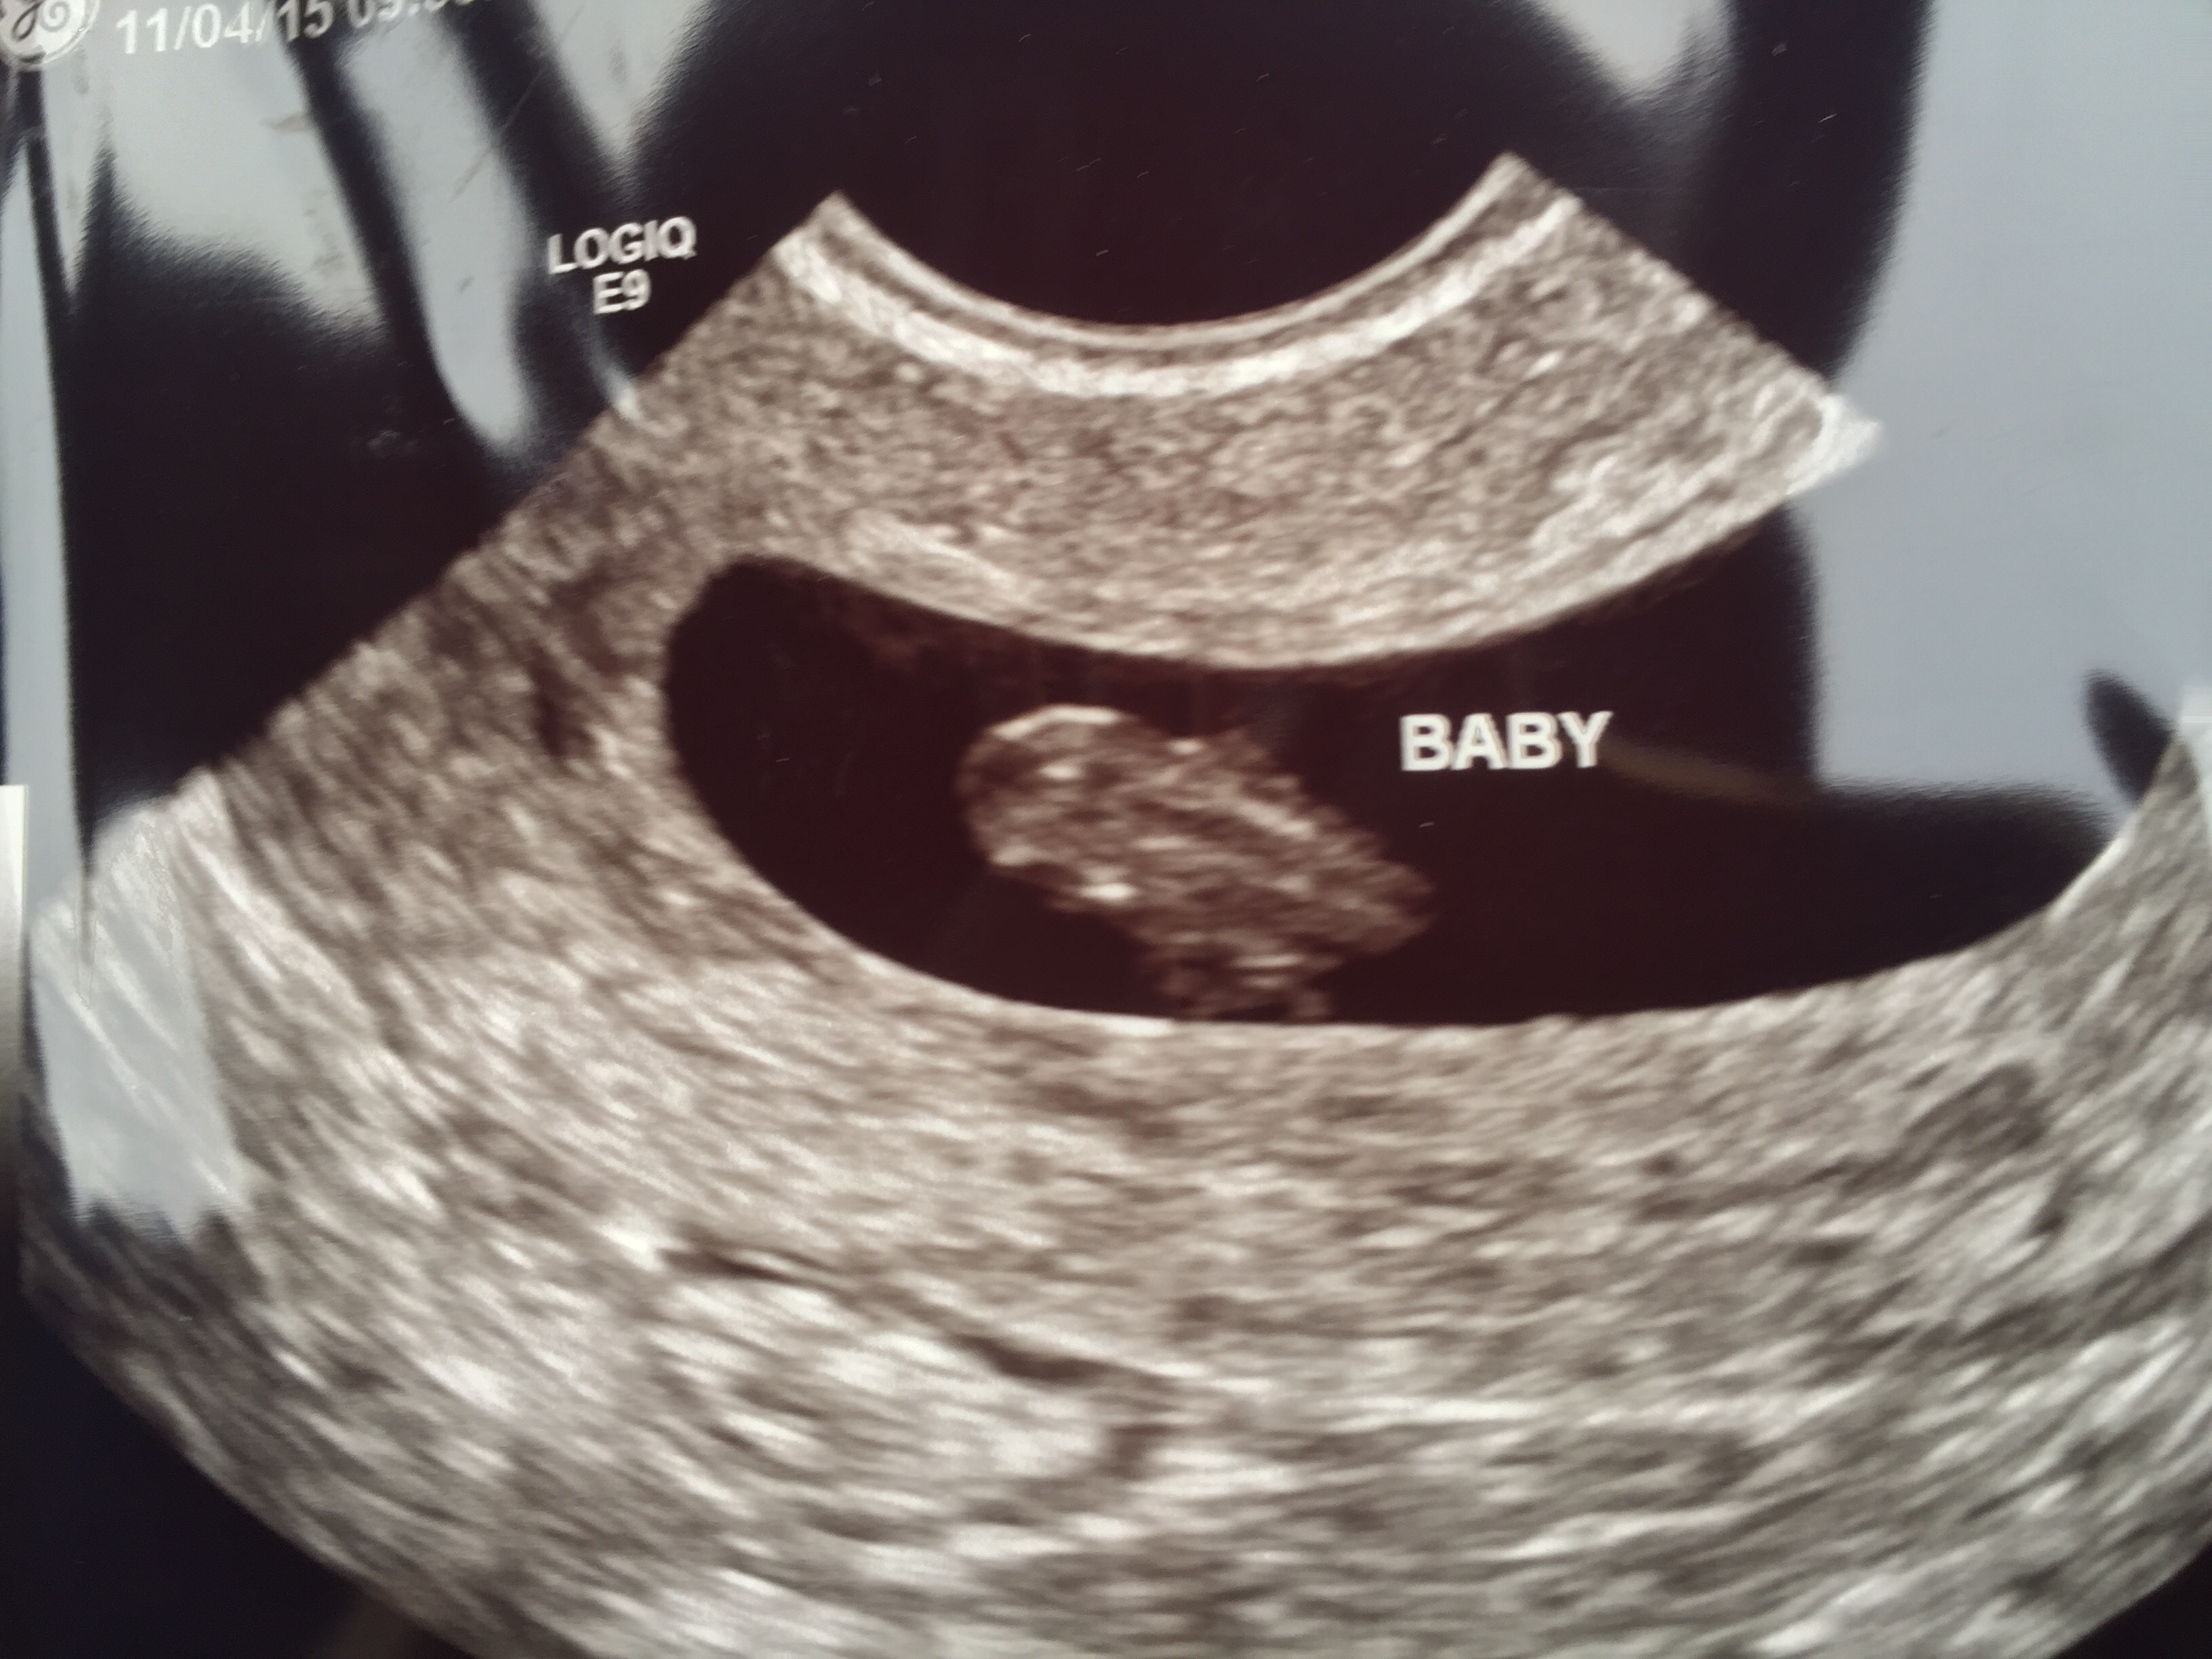

FTM... We had our first US on Monday which was also my birthday ♡ measured at 7w5d. We didn't hear the heartbeat bc the machine didn't have sound, but we could see the little heart fluttering on the monitor. So exciting, scary, emotional. Going back in about 2 weeks for the genetic screening/gender blood work & the next US will be at 12 weeks.